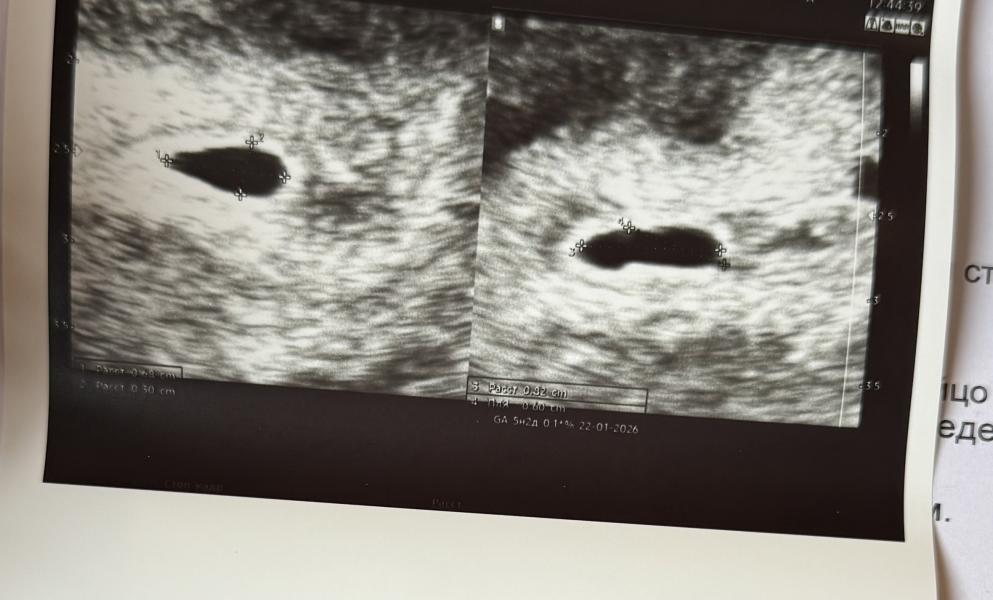

По менструации (первый день последних месячных) - акушерский срок, по размерам плодного яйца - эмбриональный (грубо говоря считается от овуляции). Разница между первым днём последних месячных и овуляцией и есть примерно две недели +/-. Поэтому у вас всё прекрасно, можно радоваться.